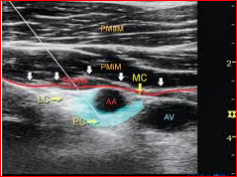

Ultrasound-guided brachial plexus blocks in pediatric anesthesia: non-systematic review<br /><br />Majid Fakhir alhamaidah*1,2, Hussein Ali Hussein 2,3, Hussein alkhfaji 2,4, Sami Raheem Hasan2, Mohammed AbdulZahra and Sasaa5Ali B. Roomi6 <br /> AL-Rifaei General Hospital, Iraq. <br />2 Department of Anesthesia, College of Health and Medical Technology, Al-Ayen University, Iraq<br />3 Nasiriya heart center<br />4 Bent AL Huda hospital, Iraq.<br />5 AL-Mustaqbal university college, department of anesthesia Babel, Iraq <br />6 College of Health and Medical Technology, Al-Ayen University, Iraq. <br />Abstract <br />Background: The ultrasound guidance for regional anesthesia has gate a widespread as a recent technique to identify, visualize, and monitoring targeted nerves, needle insertion, local anesthetic injection and distribution, catheters and adjacent anatomical structures, and helps to avoid complications such as inadvertent intravascular or intrafascicular injection in comparison to other traditional techniques.<br />Purpose of review: To show and explain if any superiority has added to brachial plexus approaches with this sonography guidance for the pediatric population over other traditional techniques in terms of increasing the success rate or reducing the complications.<br />Methods: Three authors independently searched the literature using MEDLINE and EMBASE bibliographic databases, Cochrane Central Register of Controlled Trials (CENTRAL), and manually in either the title or abstract, we also searched Google Scholar, Web of Science and reviewed the references of included trials for potentially relevant trials.<br />Results: Reviewed literature suggests that ultrasound-guided peripheral blocks reduce block performance time in comparison with nerve stimulation, increase the success rate, reduced intended LA agent, and increase the quality of the block (as measured by analgesic consumption, block duration, and pain scores). <br />Conclusion: The introduction of ultrasound imaging improved the safety profile, reduced performance time, and advanced the upper limbs block approach.<br /><br />Keywords: Ultrasound, regional block, brachial plexus, upper limb, upper extremities, pediatric anesthesia. <br /><br />Introduction <br /> Ultrasonography represents a real-time nerve visualization and drug deposition around it, other internal structures including vessels, needle, and catheter became possible to be visualized by this technique. However, its application needs some basic skills (1). Pediatric patients are unlike adults in their anatomical and physiological features, and the landmark technique is not reliable in all patients due to the variability in the age and size (2). With the advancement in sonographic technology, the success rate of blocks has increased and the recommended dose gate less than with other traditional methods for pediatric regional blocks for upper extremities with the assistance of high-frequency transducers (2). There is a tight area around nerves and plexuses in the pediatric group, which is unique to this population that gives better block under ultrasound probe. The pediatric group is not a homogenous population, but they range from neonate to an adolescent and follow to that the depth of nerves and plexuses varies with the age ranging (2).<br />Recently searched published articles showed significant advantages in the field of pediatric anesthesia of the upper limbs, involve the faster sensory and motor blockade and extended duration of sensory blockade compared with using nerve stimulation alone in children (3). Ultrasound-guided upper-extremity peripheral nerve blocks (e.g. axillary, infraclavicular, interscalene, supraclavicular) in children can be performed successfully and safely with a recommended LA dose(4). In addition to reducing the muscle contraction pain that is associated with nerve stimulation with the feasibility and efficiency of ambulatory peripheral nerve catheters in pediatrics (5). <br />Methods<br /> In this review, we searched the current literature available on MEDLINE, EMBASE, and Cochrane Evidence-Based Medicine Reviews. Furthermore, citation reviews and manual search of new journals related to pediatric anesthesia or surgery were done. We included all parallel randomized controlled trials that evaluated the effect of ultrasound guidance to perform a regional blockade technique in children. Comparative studies, question studies, case series, systematic and non-systematic reviews including one or more approaches for brachial plexus blocks were searched. Searching was limited to English language and full-text articles. Four authors read all selected articles independently and a consensus was achieved. The keywords used, alone and in combination were: ultrasound, regional block, regional anesthesia, pediatric anesthesia. A further search of older literature was deemed unsuitable, and ultrasound guidance has only become a usable modality in the last few years. The goal was to review studies about regional anesthesia in pediatrics with peripheral nerve block techniques by comparing ultrasound-guided peripheral nerve block of the upper extremities either alone or by combination with at least one other technique of nerve identification such as; anatomical landmark, paresthesia, or using of a nerve stimulator. <br /><br />Technical Consideration for Pediatrics<br /> Since body water percentage is higher with pediatrics, the identification of body structures like neurons, plexuses is better than adults under the ultrasound guidance, furthermore, bony structures have less ossification making a good quality image. Nerves, plexuses, and other structures in infants and young children are located superficially and could easy visualized by the ultrasound probe. A proper instrument to patient size and age should be available for that. Suitable needle size is needed to avoid nerve injury, and good quality transducer to gate suitable resolution for superficial structures should be prepared (2).<br />Brachial plexus block<br /> The innervation of upper extremities is derived from the brachial plexus which is composed of the union of the cervical roots from C1 to C8 and part from the T1. The main anatomical differences between pediatrics and adult populations, which increase the risk of regional lock during needle insertion with perisubclavian approaches, that the superior part of the lung and apical pleura enter the neck, above the superior thoracic aperture making the risk of plural invasion bigger than with the adults. New ultrasound technology reduced these complications by offering direct and real-time visualization of the needle and any adjacent structures with supraclavicular and infraclavicular approaches.<br /> Brachial plexus block may be achieved at several sites, the appropriateness of each block is determined by the location of the surgery, the ability to properly position the patient, and assessment of pre-existing patient morbidities. The advancement in ultrasound application techniques gave the confidence for aesthesia practitioners to approach the more proximal brachial plexus even in infants and young children, instead of the axillary site which has previously been a preferred location of brachial plexus block in pediatrics (6).<br />Since the innervation of the medial aspect of the proximal arm been separately by the intercostal brachial nerve, the brachial plexus blockade will not provide anesthesia for this area. The clinical significance of this nerve is apparent when a tourniquet is applied to the proximal arm. A transverse subcutaneous field block just below the axilla will achieve anesthesia in this region.<br />Ultrasound Guided Interscalene brachial plexus block<br /> This approach is mainly used to provide anesthesia and analgesia to the shoulder girdle and arm above the elbow, which makes interscalene approach useful for shoulder and even clavicular surgery, but generally it is inappropriate for surgery below the elbow.<br /><br /> The Interscalene block wasn’t very common in the pediatric group because of the potential adverse effects associated with this approach such as pneumothorax, intrathecal injection, and inadvertent injection into a vertebral artery. Also, this technique preferably needs to be performed by an anesthesiologist expert in nerve block. The introduction of ultrasound into clinical practice has markedly increased the use of this approach in clinical practice (7).<br /> The sensitivity of structures close to the interscalene brachial plexus makes precise needle placement imperative mandating the use of ultrasound in younger patients. In comparison with an awake adult patient and anesthetized child, there is no difference in safety issues between the two groups with interscalene approach (7). The ideal position for a child in a supine position with the arms extended alongside the thorax and the head slightly turned to the contralateral side (2).<br />Ultrasound Guided Supraclavicular Approach<br /> Supraclavicular route of brachial plexus block is extremely recommended for pediatric patients to allowing real-time visualization of the needle tip and lung parenchyma at this level, Ultrasound technique increased the safety profile of this approach, so it can be considered as ‘The Spinal of Arm’, in which local anaesthetic agent is delivered at a point where the three trunks are compactly arranged and carry entire sensory, motor and sympathetic innervations of the upper extremity (8). With the assistance of ultrasound technique, there was short time performance, less number of needle insertions, a smaller volume of the intended local anaesthetic agent, rapid onset of action, higher success rate and less complications (9). Supraclavicular approaches are indicated for the surgical procedures on the shoulder or the proximal part of the arm, forearm and the hand.<br />Ultrasound Guided Infraclavicular Approach<br /> The infraclavicular block is a brachial plexus block used as an alternative or adjunct to general anesthesia. It can be used for postoperative pain control for upper extremity surgeries by blocking the divisions or the cords of the brachial plexus, making the operations for elbow, forearm, and hand possible (8). Marhofer et al. (10) presented that infraclavicular brachial plexus blocks with Ultrasound guidance offer sensory and motor responses faster than with nerve stimulation, and longer time of sensory blockade in pediatric patients (11).<br />Ultrasound Guided Axillary Approach<br /> The axillary brachial plexus block can be used to provide reliable anesthesia and analgesia to the arm distal to the shoulder, including Surgery of the elbow, forearm, and hand; closed reduction of fractures of the elbow, forearm, and hand for postreduction pain relief. <br /> Recent Literature reviews showed that the axillary block is the most common, easiest and safest method in pediatric patients, with the goal of blocking the terminal branches of the brachial plexus. It has the least complications when compared with the other blocks for the upper limb. Inadvertent arterial puncture and intraneural injection are the most undesirable feared complication. It is usually thought intraneural injection is the main cause of permanent nerve damage and mostly undetected in the patient under general anesthesia. (11)<br />Ultrasound Guide for Elbow and Forearm<br /> Brachial plexus blocks by elbow and forearm approaches are not so common approaches in pediatrics but usually induced as supporting methods for partially failed brachial blocks. Ultrasound technology extends the indications of these approaches. Median and ulnar nerves are located superficially and can be blocked easily at any point of their way from the wrist to the axilla, but the operator should be carefully oriented to differentiate between the nerves and the tendons at the level of the wrist since they have similar view under ultrasound probe1. A complete block can be gain with a small volume of local anesthetic agents. (11)<br />Conclusion <br /> Depending on the outcomes gained from the reviewed studies and materials, the authors concluded with consent that ultrasound guidance increases the success rate for brachial plexus blocks applied to pediatric patients. These studies showed decreased performance time, good visualization of the needles, catheters, adjacent anatomical structures, and local anesthetic distribution. With the assistance of ultrasound guidance, the inadvertent blood vessel punctures were significantly reduced. (12). The use of ultrasonography to guide the peripheral nerve blocks in the pediatric population made these procedures safer, either alone or in concomitant with the traditional techniques. (13,14), ultrasound guidance facilitated the catheter placement for continuous nerve blocks (12) and induced less intraoperative consumption of opioids compared with other techniques (15) Less volume of local anesthetic was sufficient to perform the block (15). Similar block success, postoperative sensory block durations, and pain scores could be obtained during infraclavicular brachial plexus in pediatric patients with lower local anesthetic volumes (16). Recently reviewed studies showed that the ultrasound technique has grown to be the standard for peripheral analgesia and pain control (17).<br />References<br />1. Ilfeld BM, Wright TW, Enneking KF, Morey TE. Joint range of motion after total shoulder arthroplasty with and without a continuous interscalene nerve block: a retrospective, case-control study. Regional Anesthesia & Pain Medicine. 2005;30(5):429-33.<br />2. Delvi MB. Ultrasound-guided peripheral and truncal blocks in pediatric patients. Saudi journal of anaesthesia. 2011;5(2):208.<br />3. Tsui BC, Suresh S. Ultrasound imaging for regional anesthesia in infants, children, and adolescentsa review of current literature and its application in the practice of extremity and trunk blocks. Anesthesiology: The Journal of the American Society of Anesthesiologists. 2010;112(2):473-92.<br />4. Suresh S, Ecoffey C, Bosenberg A, Lonnqvist P-A, De Oliveira GS, de Leon Casasola O, et al. The European Society of regional anaesthesia and pain Therapy/American Society of regional anesthesia and Pain medicine recommendations on local anesthetics and adjuvants dosage in pediatric regional anesthesia. Reg Anesth Pain Med. 2018;43(2):211-6.<br />5. Perlas A, Lobo G, Lo N, Brull R, Chan VW, Karkhanis R. Ultrasound-guided supraclavicular block: outcome of 510 consecutive cases. Regional Anesthesia & Pain Medicine. 2009;34(2):171-6--6.<br />6. Veneziano G, Betran R, Bhalla T. Peripheral regional anesthesia in infants and children: an update. Anaesthesia, Pain & Intensive Care. 2019:267-73.<br />7. Taenzer A, Walker BJ, Bosenberg AT, Krane EJ, Martin LD, Polaner DM, et al. Interscalene Brachial Plexus Blocks Under General Anesthesia in Children: Is This Safe Practice? Reg Anesth Pain Med. 2014;39(6):502-5.<br />8. Ríos-Medina AM, Caicedo-Salazar J, Vásquez-Sadder MI, Aguirre-Ospina OD, González MP. Regional anesthesia in pediatrics–Non-systematic literature review. Colombian Journal of Anesthesiology. 2015;43(3):204-13.<br />9. Amiri HR, Espandar R. Upper extremity surgery in younger children under ultrasound-guided supraclavicular brachial plexus block: a case series. Journal of children's orthopaedics. 2011;5(1):5-9.<br />10. Marhofer P, Sitzwohl C, Greher M, Kapral S. Ultrasound guidance for infraclavicular brachial plexus anaesthesia in children. Anaesthesia. 2004;59(7):642-6.<br />11. Dalens B. Regional anesthesia in children. Anesthesia & Analgesia. 1989;68(5):654-72.<br />12. Guay J, Suresh S, Kopp S. The use of ultrasound guidance for perioperative neuraxial and peripheral nerve blocks in children. Cochrane Database of Systematic Reviews. 2019(2).<br />13. Krodel DJ, Marcelino R, Sawardekar A, Suresh S. Pediatric regional anesthesia: A review and Update. Current Anesthesiology Reports. 2017;7(2):227-37.<br />14. Frenkel O, Liebmann O, Fischer JW. Ultrasound-guided forearm nerve blocks in kids: a novel method for pain control in the treatment of hand-injured pediatric patients in the emergency department. Pediatric emergency care. 2015;31(4):255-9.<br />15. Lam DK, Corry GN, Tsui BC. Evidence for the use of ultrasound imaging in pediatric regional anesthesia: a systematic review. 2016.<br />16. Ince I, Aksoy M, Dostbil A, Tuncer K. Can we use lower volume of local anesthetic for infraclavicular brachial plexus nerve block under ultrasound guidance in children? Journal of clinical anesthesia. 2017;41:132-6.<br />17. Yayık AM, Ekinci M, Gölboyu BE, Ergüney ÖD, Çelikkaya ME, Ahıskalıoğlu EO, et al. Pediyatrik inguinal herni tamirinde ultrasonografi eşliğinde yapılan transversus abdominis plan bloğu ile yara yeri infiltrasyonunun karşılaştırılması: Randomize klinik çalışma. 2017.<br /><br />